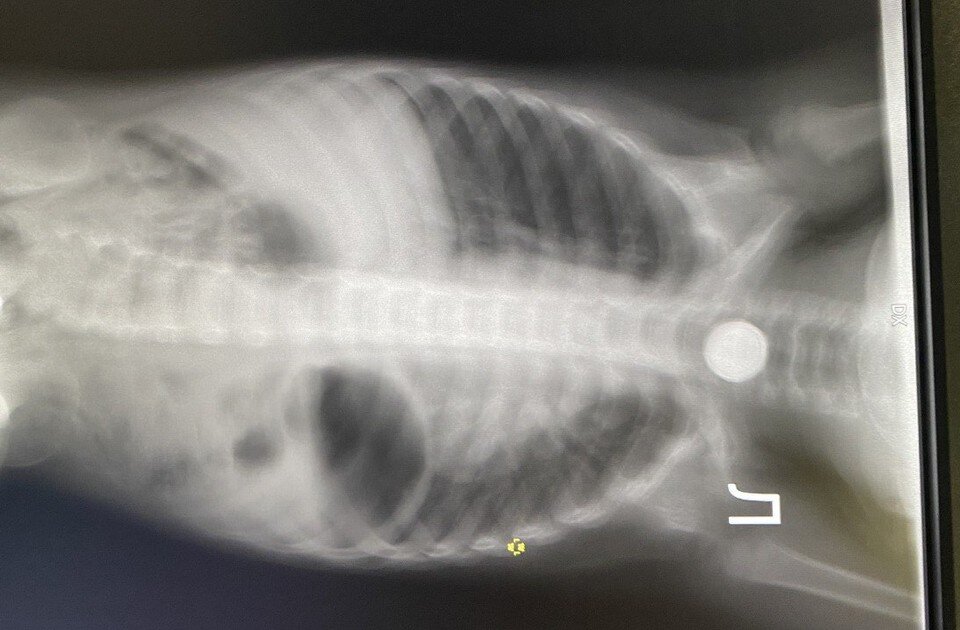

Врачам нередко приходится доставать инородные предметы. Фото: Городская больница № 20.

По словам хирурга, дети часто проглатывают монеты. Фото: Городская больница № 20.

Ожидаема угроза колющих предметов, которые, например, могут повредить стенки внутренних органов. Недавно в «двадцатку» поступил ребенок с клиникой острого аппендицита. Во время операции врачи выяснили, что он проглотил зубочистку.

- Была обнаружена перфорация аппендикса из-за проглоченной ранее зубочистки. Все обошлось, ребенок выздоровел, -комментирует этот случай врач.